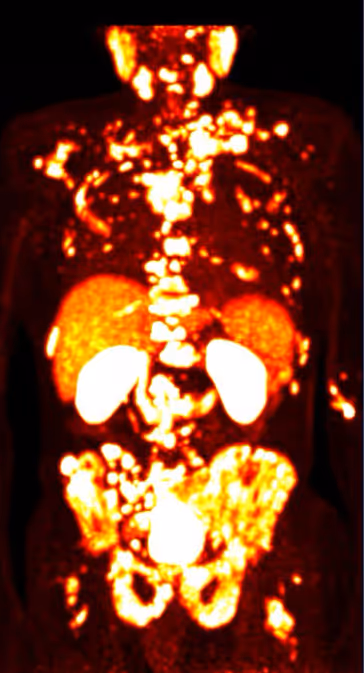

As a first step, PSMA PET/CT imaging is used to determine whether the cancer cells express sufficient PSMA. This examination shows where active tumor cells are located in the body. If this biological requirement is met, radioligand therapy can be applied in a targeted manner.

A prerequisite for this targeted effect is the prior confirmation of sufficient PSMA expression using PSMA PET/CT imaging.

A key prerequisite is that the tumor cells express sufficient PSMA. This is verified using PSMA PET/CT imaging. Only if this biological condition is met can the therapy be expected to work effectively.

Before treatment, PSMA PET/CT imaging is used to determine whether tumor cells express sufficient PSMA. This approach increases the likelihood that the therapy will be effective. A detailed medical evaluation is carried out as part of the indication for PSMA therapy.

For the therapy to be effective, tumor cells must express sufficient PSMA. If expression is low or the target structure is absent, treatment efficacy may be limited. This is assessed in advance using PSMA PET/CT imaging.

Disease progression and treatment response are monitored through laboratory tests (such as PSA levels) as well as imaging studies. PSMA PET/CT is often used to objectively evaluate the response.

First, a PSMA PET/CT scan is performed to determine whether the tumor cells sufficiently express PSMA. Based on these findings, a decision is made as to whether the therapy is appropriate.